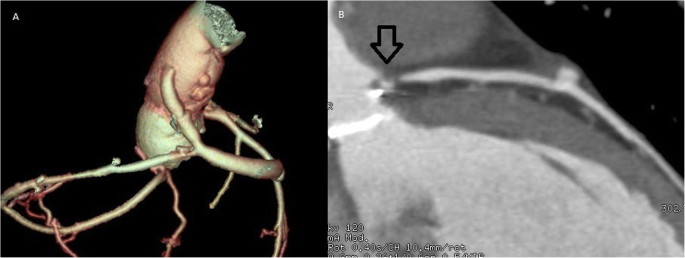

Patient is a petite 35-year-old vegan female with past medical history of systemic lupus erythematosus (SLE), antiphospholipid syndrome (APS), and deep vein thrombosis complicated with pulmonary embolism for which she received rivaroxaban. On routine medical examination, while she was completely asymptomatic, a holosystolic murmur was detected, thus, echocardiography was requested. It revealed a dilated left ventricle with mild hypertrophy and an ejection fraction of 58%. Her aortic leaflets were thickened with limited mobility, her maximum aortic velocity was 4.36 m/s, and the mean gradient was 45 mmHg. A severe regurgitant flow was at the aortic valve confirming severe aortic insufficiency (AI) and moderate aortic stenosis (AS). Mixed aortic valve disease was diagnosed and due to her clinical background, surgery was decided, nonetheless anxiety and fear caused her to refuse surgery. One year passed and although she remained asymptomatic, her condition worsened, maximum aortic velocity was 5.36 m/s, the mean gradient was 60 mmHg, and aortic valve area was 0.9 cm2. Also noted was an increase in the left ventricular diastolic diameter due to severe aortic Insufficiency (Fig. 1a). After great help from her family and psychology treatment, surgery was accepted. Sternotomy and cardiopulmonary bypass (CPB) were completed after a dose of 300 U/kg was administered and the ACT (activated clotting time) was over 480 s, the ACT was monitored every 30 min. Cardiac arrest was achieved via antegrade and retrograde cardioplegia, the temperature was kept at 35 C and cold cardioplegia was administrated every 10 min. Aortotomy was done. The aortic valve was visualized, revealing fibrous and stenotic aortic leaflets. The leaflets were excised, and a 17-mm prosthetic aortic valve was placed (St. Jude Medical, Inc., St. Paul, Minn) after we measured her aortic annulus diameter (18 mm) (Fig. 1b). Both coronary vessels were identified and spared during the valve replacement. Once the valve was sewn and placed, the aortotomy was closed with a 5–0 polypropylene suture in a two-layer fashion. Before removing the aortic cross-clamp warm blood retrograde cardioplegia was given. The cross-clamp was removed, and the heart reverted in sinus rhythm. With a transesophageal echocardiogram (TEE) the prosthetic valve was evaluated and didn’t exhibit any problems (Fig. 2a). The patient was weaned off CPB using a 50 mg test dose of protamine. With no hemodynamic instability from this dose, the rest of the protamine was given slowly over 15 min. While finishing the procedure as the sternal wires were placed, the patient suddenly suffered from severe hypotension, bradycardia, and sudden cardiac arrest. The sternal wires were removed, and cardiopulmonary resuscitation was started immediately with open cardiac massage and repeated direct defibrillation with 20 joules, heparin was given, aortic and atrial cannulation was done during the cardiac massage and the patient was placed again under CPB. Since the heart had multiple zones of hypokinesia and akinesia in both ventricles. ECG at that time registered pulseless electrical activity. Using TEE, we confirmed regional wall motion abnormalities in both ventricles (Fig. 2b and Supplementary Video (1)). The aortic prosthesis had a normal function and we suspected a coronary perfusion problem. Since it was difficult to locate the exact coronary lesion, we decided to perform an immediate coronary artery bypass graft (CABG) surgery. We used saphenous vein grafts to the left anterior descending and the right coronary arteries. The myocardium showed signs of definite clinical improvement following revascularization. Inotropic and vasoactive agents were partially weaned off along with CPB, the patient was transferred to the intensive care unit for close monitoring. Neurological complications were suspected due to the cardiac arrest, nonetheless, the patient satisfactorily recovered from the procedure without any neurological deficits. Her postoperative course was uneventful despite developing posterior wall MI (myocardial infarction) with preserved ejection fraction, she was fully aware on her first postoperative day and never showed signs of neurological complications (Fig. 2c and Supplementary Video (2)). Anticoagulation was managed with low-molecular-weight-heparin and warfarin was continued until the international normalized ratio (INR) achieved a value ranging between 2.5 and 3.5. She was discharged on her eighth postoperative day. Anticoagulation (Unfractionated heparin and a vitamin-K antagonist) was difficult due to her diet, but she remained on close follow-up controls, with hematologist. A Computed tomography (CT)-coronary angiogram at that time revealed total ostial obstruction of both coronary arteries trunks, and adequate flow through both saphenous vein grafts. On follow-ups, patient was doing well (Fig. 3a, b).

Nonetheless 3 months after surgery she suddenly experienced acute chest pain, shortness of breath, nausea, and fatigue thus was brought immediately to the emergency room. On clinical examination, a tachycardic and diaphoretic patient was encountered. An electrocardiogram (EKG) detected an anterior myocardial infarction with ST-elevation, along with troponin values above 130 pg/L and INR of 2.27. Femoral access was achieved, and percutaneous coronary intervention was decided. On coronariography, (Fig. 4a, b) the right native coronary artery appeared normal and to our surprise it recanalized spontaneously. However, the left coronary artery occlusion persisted and there was a severe thrombotic stenosis of the left saphenous vein bypass. The right saphenous vein bypass to the right coronary artery was also totally occluded. After successful intraortic balloon pump (IABP) insertion a stent was placed on the saphenous vein graft achieving adequate blood flow improving the patient’s condition. Transthoracic echocardiogram revealed anterolateral hypokinesia of the left ventricle, with an ejection fraction of 45%. After this procedure, the patient fully recovered and had no cardiac symptoms. She was discharged under close anticoagulation surveillance. Three months later and due to the fact that the patient had experienced early graft failure and her young age, it was decided to perform percutaneous revascularization of the main left coronary trunk which was performed successfully (Fig. 5a) with intravascular ultrasound guidance. She completely recovered from the procedure and 1 year after surgery on regular follow-ups, the patient is doing well without any complications.